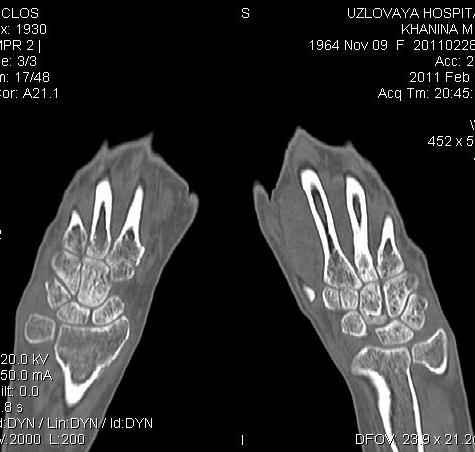

Уважаемые коллеги.Прошу обсудить случай лечения перелома дистального метаэпифиза лучевой кости. Ситуация скандальная и крайне неблагоприятная. Больная с патологической обстоятельностью мышления, склонностью к сутяжничеству, патологическими умозаключениями, не поддающимися коррекции (см. психиатрию, правда офиц. диагноза нет). В данном случае есть ряд ошибок с нашей стороны, прежде всего в отношении качества ведения документации (за что получил административное взыскание, по делом мне дураку). В остальном- придерживались в лечении подхода классический советской школы. Так как умную операцию…… сами знаете… 15.12- перелом луча в Москве. Там же репозиция, гипс. Дальнейшее лечение у нас в ЦРБ. 20.12.- вторичное смещение в гипсе21.12- под внутривенным наркозом- репозиция, гипсовая лонгета. Дальше начинается самое интересное. После репозиции больная заявила, что я (репозицию делал я) порвал ей все связки в суставе, посинел у нее 5 палец, якобы я за него тянул и т. д. На самом деле на 2 сутки после репозиции рука немного отекла и было незначительное сдавление гипсом, который был ослаблен. Дальнейшее лечение консервативное. Через 6 недель- гипс снят, назначено ЛФК. Пациентка крайне недовольна. Говорит, что на снимке у нее выступает кость, я ей сломал руку и.т.д. В общем началось. Пациентка прочитала в интернете наверное все, что есть по данной травме.По заключениями рентгенологов и консультанта из КДЦ областной больницы - стояние отломков допустимое. Объективно говоря- снижена высота лучевой кости, диастаз лучелоктевого сочленения, и не сросся шиловидный отросток. однако на РКТ при сравнении с другой стороной- разница незначительная. Дальше в одной из больниц нашей области и одной из больниц Москвы (вроде бы КГБ 53) врачи сказали, что репозиция сделана плохо. Нужна операция (восстановить длину лучевой кости), даже один из них предложил РЕДРЕССАЦИЮ (хи-хи) с наложением аппарата Илизарова. Что это для данной больной- радость неописанная. (см. описание психического статуса). Ничем другим, кроме зарабатывания дешевого авторитета объяснить данный факт не могу.Кстати, у больной еще нейропатия локтевого нерва.Для разрешения конфликта больная направлена на консультацию в ЦИТО на 03.03.11.

Теперь вопросы: 1.Прошу объективно оценить качество нашей репозиции на момент 21.12. (неужели так плохо?). Что на снимках при снятии гипса- сам вижу. 2. сравнить снимки РКТ (с двух сторон)- так ли велико укорочение лучевой кости и лучелоктевой диастаз. 3. Ваши мнения, в отношении целесообразности оперативного лечения учитывая ВСЕ вышеизложенное. 4. На всякий случай для суда- мог ли я тракцией в 2- 3 кг за 1 и 2 пальцы под внутривенным наркозом неправильно вколотить отломки и травмировать локтевой нерв. Кстати, в США если врач пациенту говорит, что его плохо лечили- то этого врача лишают лицензии. У нас наооборот- обгадить другого милое дело. И это процветает. От себя же могу сказать, что никто в нашем отделении так не поступает. Коллеги, будьте осторожны в своих высказываниях. От осложнений и ошибок никто не застрахован. А в данном случае многое будет зависеть от заключения консультантов поликлиники ЦИТО, куда больная направлена областным травматологом на 03.03 для решения вопроса о дальнейшей тактики лечения. С уважением ко всему травматологическому сообществу Дедок Михаил.